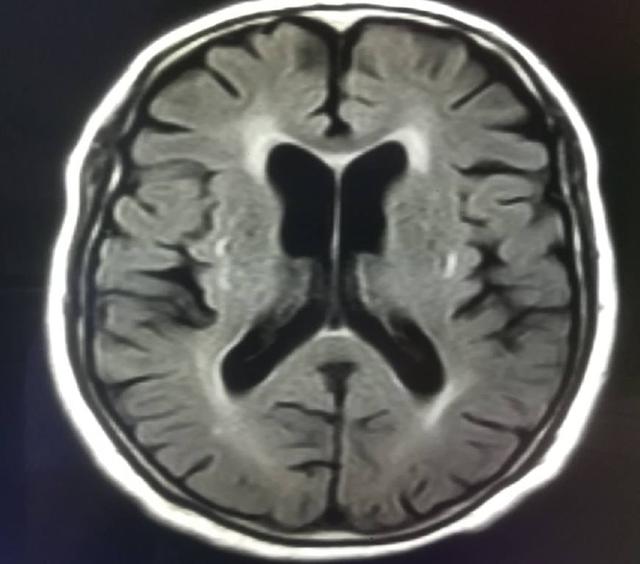

腦萎縮也分為生理性的腦萎縮和病理的腦萎縮,很多老年人隨著年齡的增加,大腦的組織細胞會逐漸縮小,會形成生理性的腦萎縮,這一類患者在臨床上往往沒有什么癥狀。如果是病理性的腦萎縮,患者會出現(xiàn)認知功能的障礙等,那么這時,腦萎縮不治會自愈嗎?

如果出現(xiàn)輕度的腦萎縮,可以出現(xiàn)腦組織結(jié)構(gòu)的體積縮小,細胞數(shù)目減少。一旦患有這種疾病的話,是不可能自愈的,即使積極的通過飲食生活調(diào)理,經(jīng)過用藥治療,也只能緩解臨床癥狀,腦萎縮的組織是不太可能完全恢復(fù)。但是通過治療,可以有效的預(yù)防腦萎縮進一步進展。

患者一旦出現(xiàn)了記憶力減退的問題,這種老年人就要及時的就診醫(yī)院,做磁共振的檢查,做智能量表的評估,要積極的尋找病因,針對病因進行治療,同時可以服用腦復(fù)康等藥物進行積極的治療,延緩患者疾病的進展。